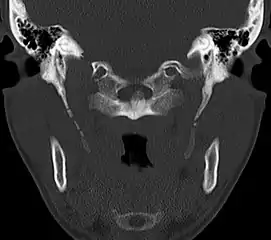

Radiograph, lateral view showing joint-like formation in ossified stylohyoid ligament CT scan, coronal section showing bilateral extended styloid process and stylohyoid ligament ossification (incidental finding)

CT scan, coronal section showing bilateral extended styloid process and stylohyoid ligament ossification (incidental finding) 3D-reconstructed CT scan showing bilateral stylohyoid ligament ossification

Diagnosis is suspected when a patient presents with the symptoms of the classic form of "Eagle syndrome" e.g. unilateral neck pain, sore throat or tinnitus. Sometimes the tip of the styloid process is palpable in the back of the throat. The diagnosis of the vascular type is more difficult and requires an expert opinion. One should have a high level of suspicion when neurological symptoms occur upon head rotation. Symptoms tend to be worsened on bimanual palpation of the styloid through the tonsillar bed. They may be relieved by infiltration of lidocaine into the tonsillar bed. Because of the proximity of several large vascular structures in this area this procedure should not be considered to be risk free.

Imaging is important and is diagnostic. Visualizing the styloid process on a CT scan with 3D reconstruction is the suggested imaging technique.[12] The enlarged styloid may be visible on an orthopantogram or a lateral soft tissue X ray of the neck.